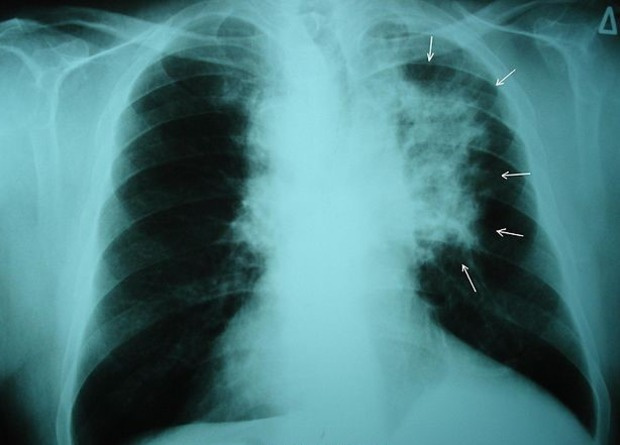

Ежегодный скрининг среди предрасположенных к раку людей проводят для многих видов злокачественных образований, но не всегда понятно, можно ли предотвратить смерти от рака, если диагностировать его на ранней стадии. Так британские ученые обнаружили, что скрининг, определяющий онкомаркер рака яичников, не снижает смертность от этого заболевания. В то же время для рака легких лучевые методы диагностики на ранних стадиях заболевания, по всей видимости, помогают снизить смертность — такие результаты получили исследователи, которые проводили периодический скрининг на когорте датчан и бельгийцев.